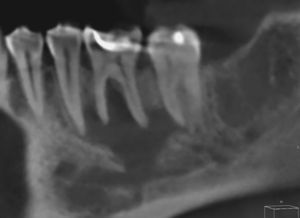

En la ortopantomografía de este paciente se observa una zona hipodensa localizada (aclaramiento) perirradicular en el diente 36 (fig. 1). La estructura mencionada abarca desde el ápice mesial del diente 37 hasta el ápice del diente 35. En la tomografía volumétrica dental adquirida consecutivamente, la masa hipodensa ocupante del espacio se extiende hacia caudal hasta el conducto mandibular del lado izquierdo y hacia bucal hasta el hueso compacto bucal (figs. 2 y 3). Este presenta dos perforaciones ovales a la altura del diente 36 (fig. 4). El techo del conducto mandibular del lado izquierdo no es apreciable en un tramo de aproximadamente 7mm. Se observan íntegramente las raíces de los dientes 35, 36 y 37.

Debido a las dimensiones del proceso y a la presencia de perforación del hueso compacto bucal, además de un quiste se sospechó como diagnóstico diferencial la presencia de un granuloma eosinófilo. En la preparación histológica de la muestra obtenida por resección pudo confirmarse un quiste radicular.